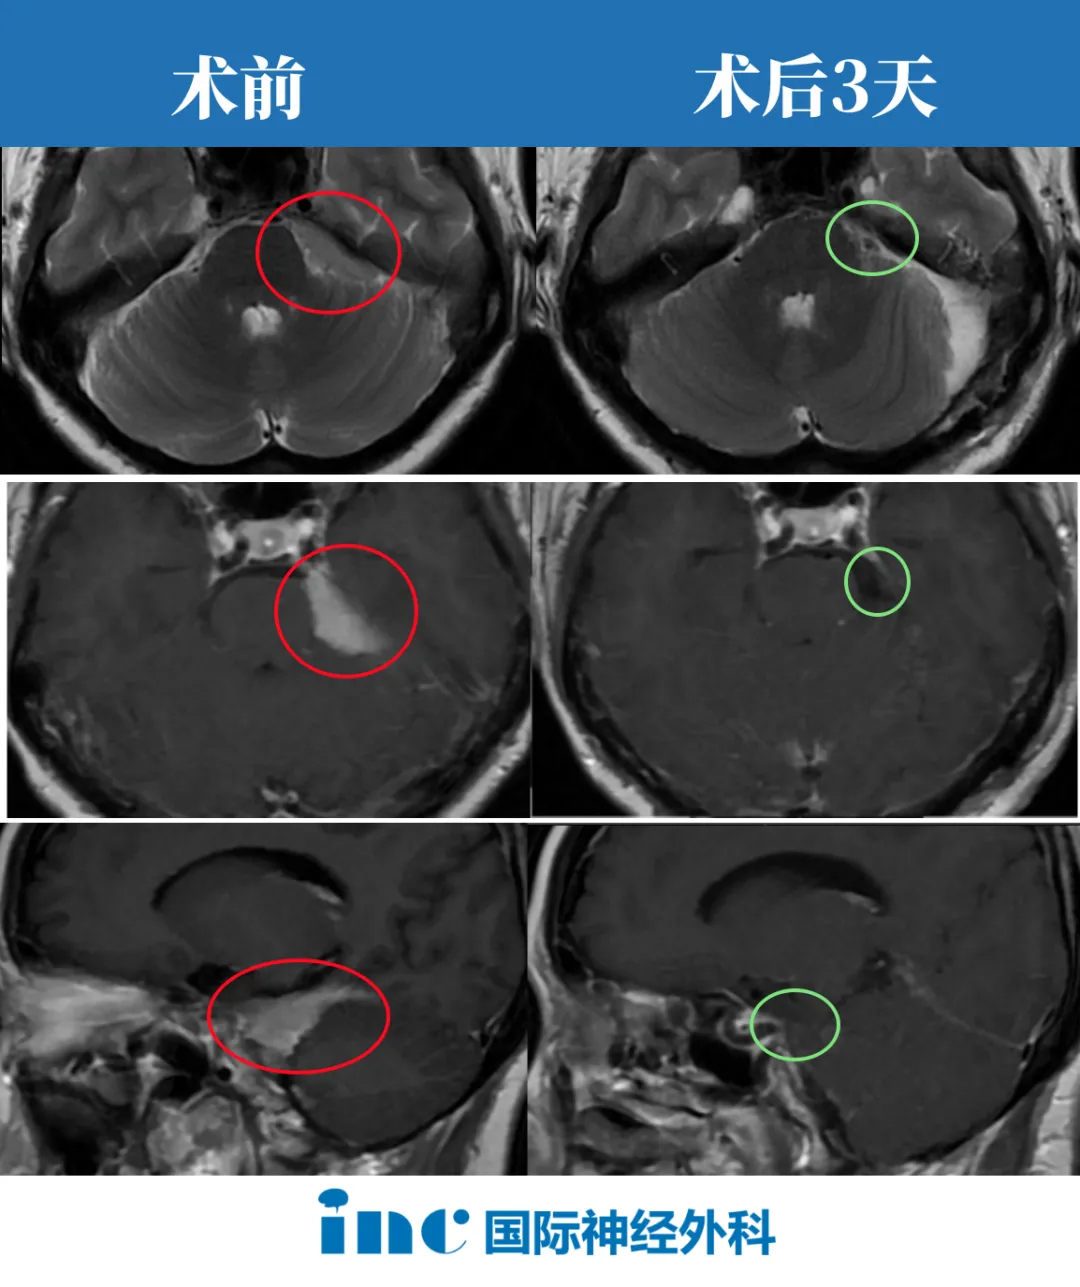

50岁的方女士自从2023年6月由于偏头痛查出左侧鞍旁、左侧CPA、小脑幕下缘占位脑膜瘤;双侧额叶缺血性脑白质病变。半年来他们从西北走到北京,四处寻医。从保守到手术,听到了众多方案。然而“手术风险大”、“术后有复视等风险”、“肿瘤位置难可能切不干净”,这些话一次次刺痛了一家人的心。

▼方女士术前影像

2024年1月14日,世界脑干颅底手术大咖巴教授顺利完成这台高难度脑膜瘤手术。

“病人现在不应该担心,但也应该每年做一次核磁共振控制来监测情况。”——50岁的方女士在高难度脑膜瘤全切手术3个月后,再次收到了巴教授从德国发来的好消息,巴教授在收到术后最新核磁影像复查资料后表示“脑膜瘤被全切了,手术没有负作用”。方女士和家人也终于再次放下了心。